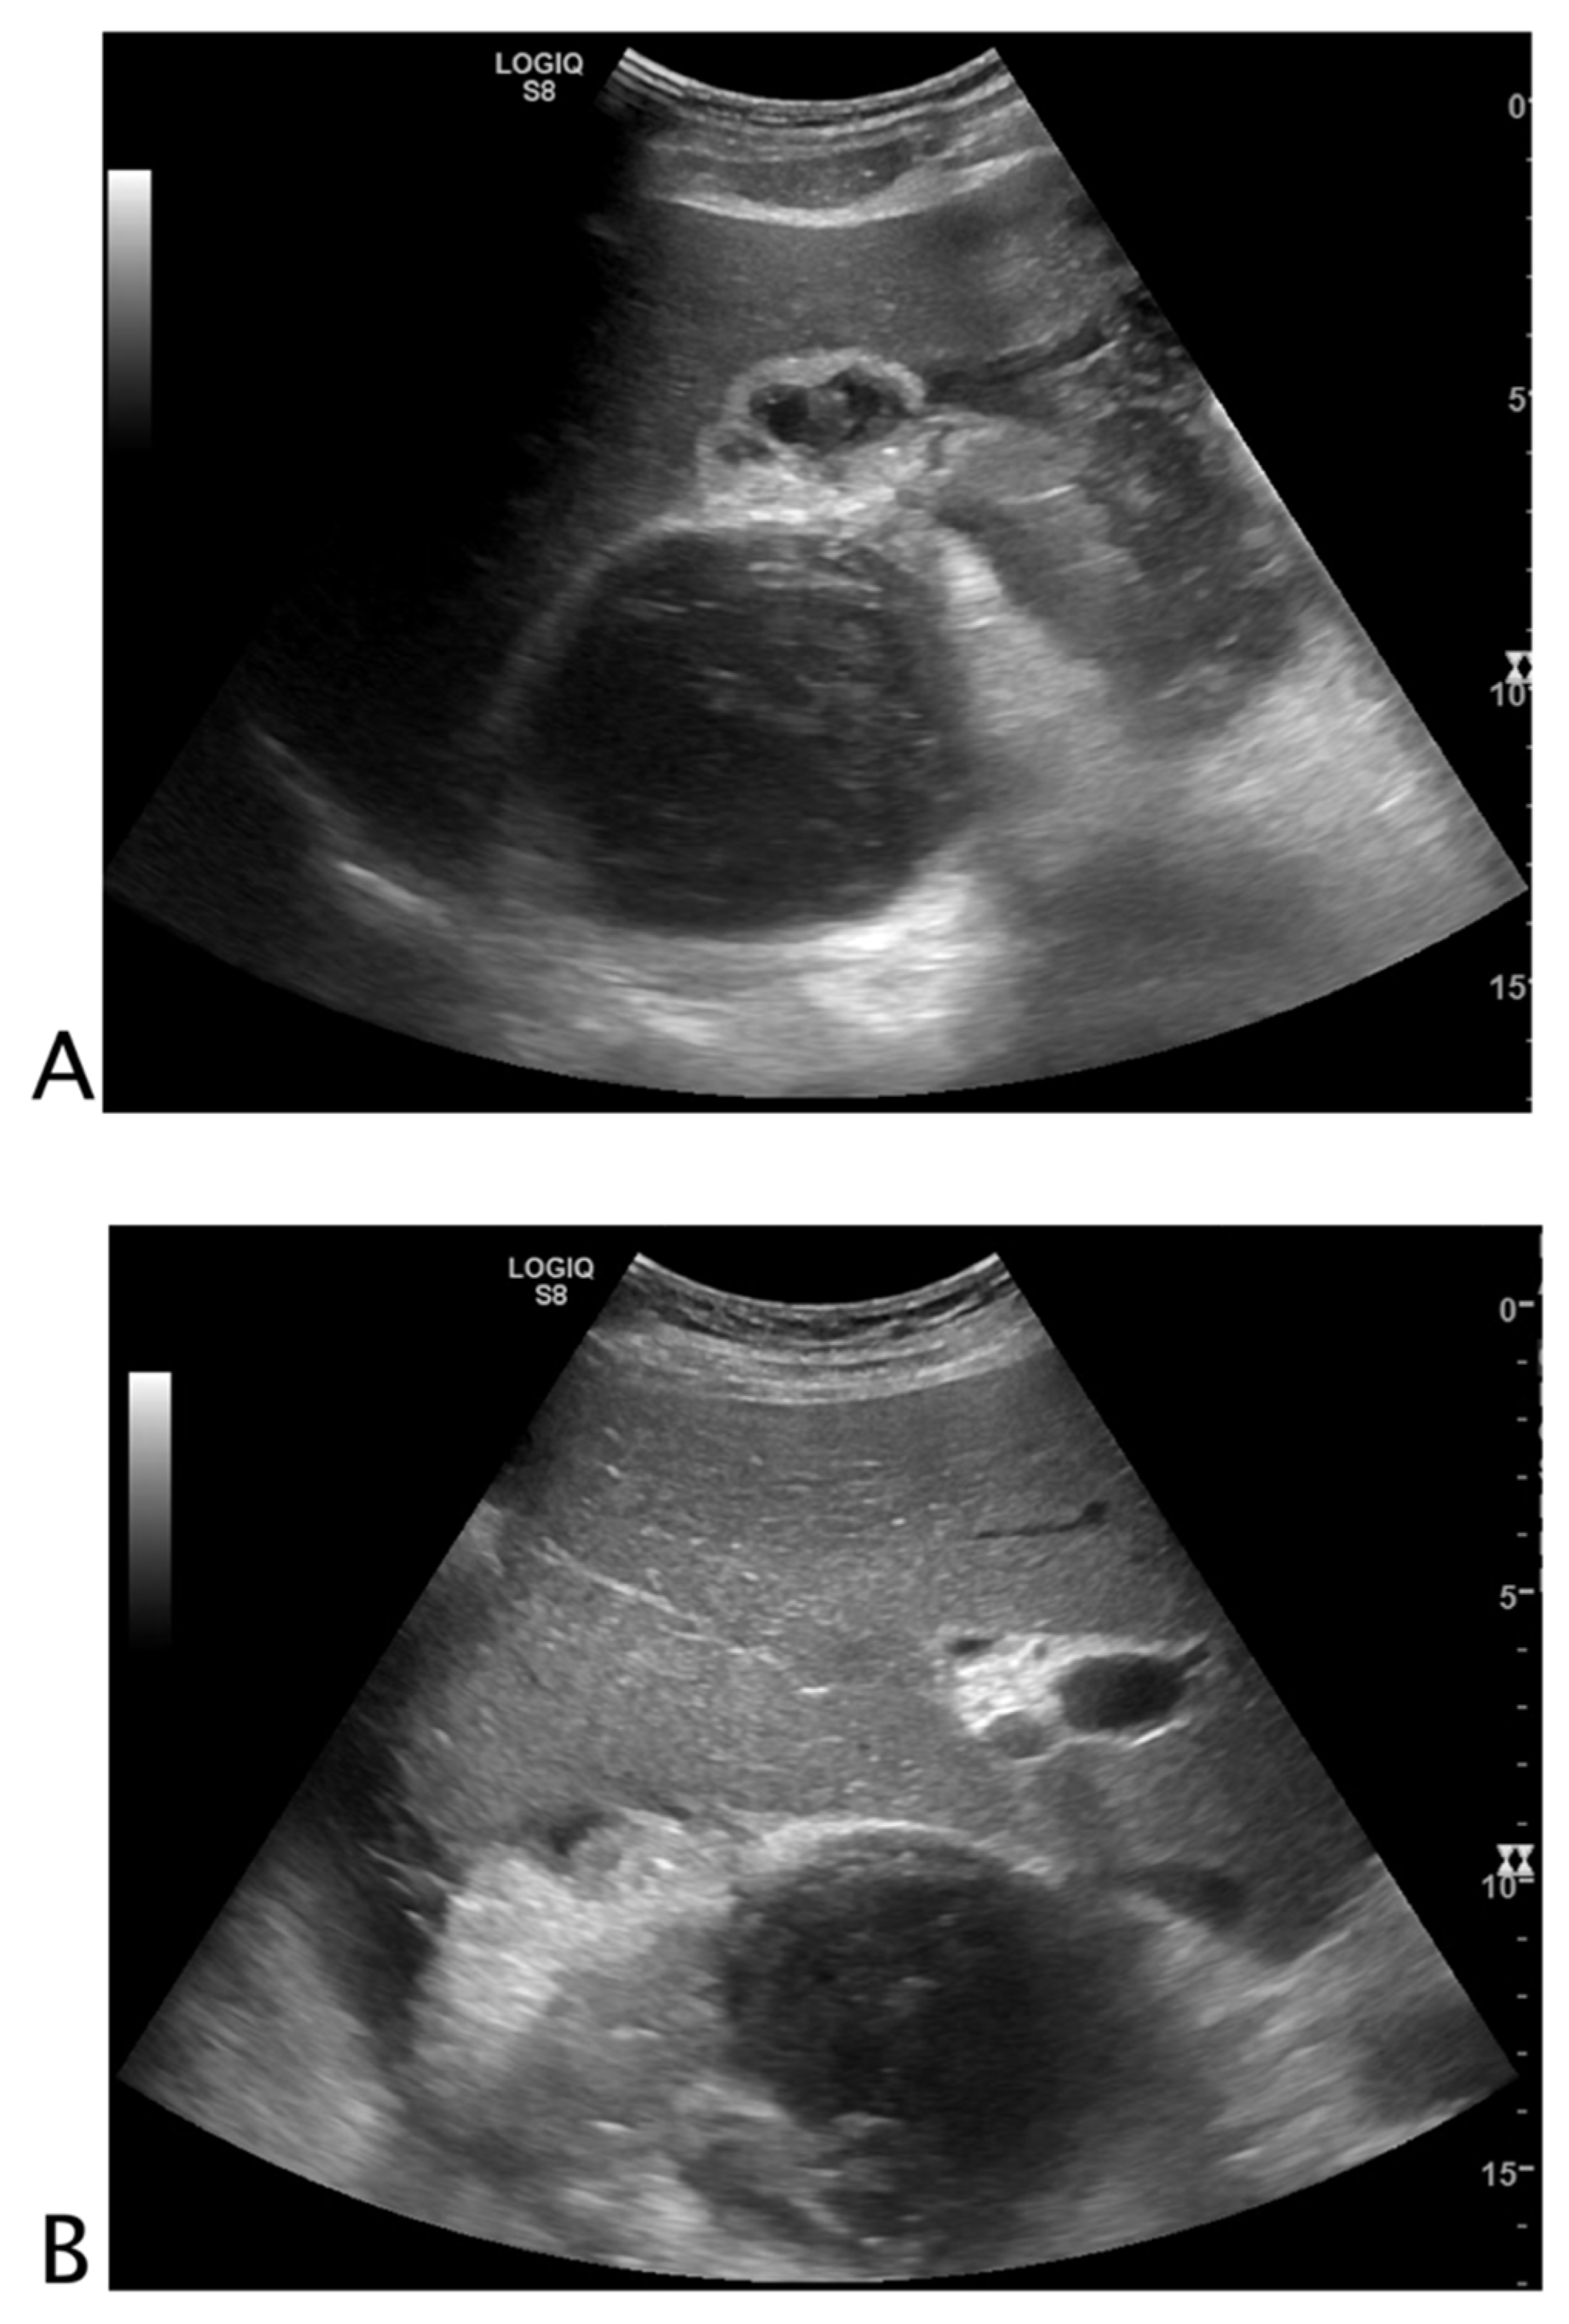

2.2. Looking to See If There Is Too Much Black Where It Is Normally Present

2.2.1. Vessels

2.2.2. Urinary Tract

2.2.3. Biliary Tract

2.2.4. Bowel